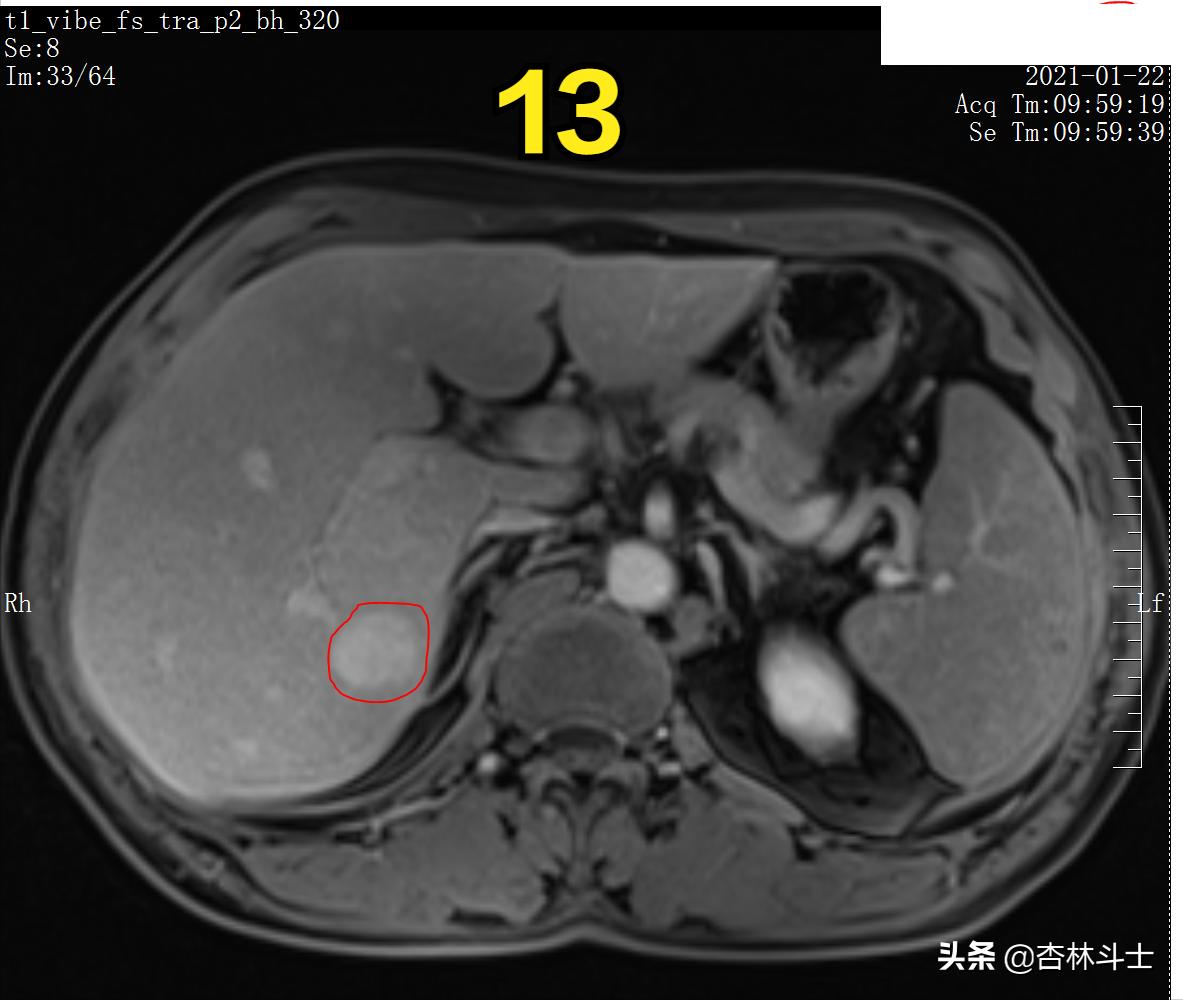

图12 T1加权压脂平衡期

图13 T1加权压脂平衡期

图12-16 持续20余分钟,病灶内仍有特异性对比剂。